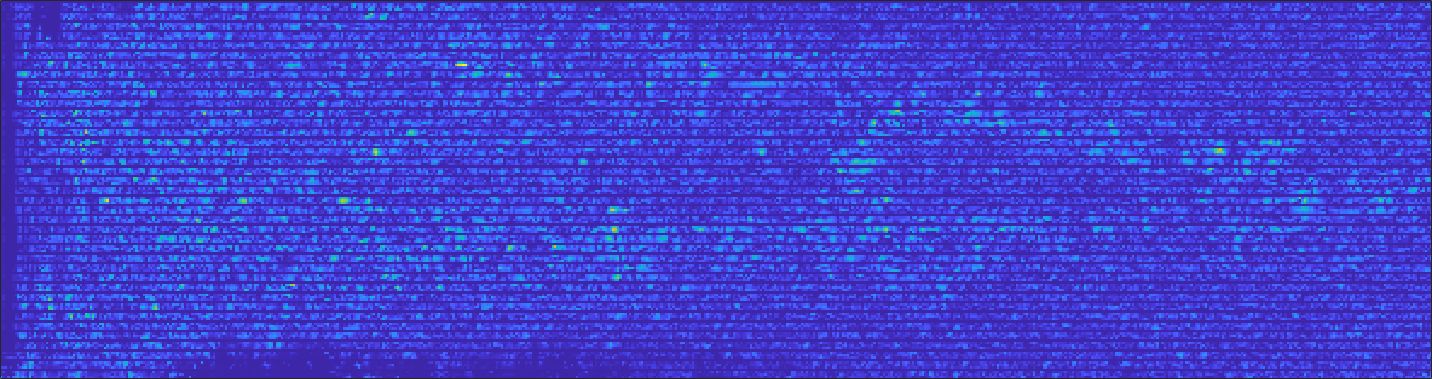

4.2 Comparison with previous work

We address both the comparison among state-of-the-art algorithms that are used for the selection of the up-sampling method of our framework and the comparison of our results with previous work. Among up-sampling STAR methods, we test four methods belonging to different classes: Cubic Convolution [Key81], a kernel-based interpolating method; Enhanced Deep Residual Networks - EDSR [LSK+17], a learning-based method trained on generic images; Enhanced Super-Resolution Generative Adversarial Network Plus - ESRGAN+ [RR20], a learning-based GAN method, specialised on US images with a dedicated training; Single Image Super Resolution - SISR [PE14], an up-sampling method which exploits sparse representations. We evaluate the up-sampling results of the selected methods on different anatomical districts and resolutions: obstetric district with 0.5X down-sampling (Fig. 12); abdominal district with 0.25X down-sampling (Fig. 13). Fig. 14 shows the error image between target and SOTA super-resolution on both 2X and 4X up-sampling, with the maximum error value in the range : Cubic convolution has visually the best results in terms of approximation error. Furthermore, our method improves the error image results with respect to Cubic convolution, improving the approximation of the target image, including the maximum error. All the error images of each up-sampling factor are represented with the same colour scale to better visualise the differences among the methods.

Tables 1, 2, 3 summarise the comparison with the PSNR, SSIM, and MAE metrics on a test data set of 200 images. Cubic convolution has a mean PSNR value of 36.52 and 42.17 for 2X and 4X upsampling, respectively. According to these results, we select Cubic convolution as the best method for the up-sampling of US images. This method interpolates the missing lines, without generating artefacts. In comparison, our method improves the results of previous work (Fig. 12, Fig. 13, Table 1), with a mean PSNR value of 37.00 and 44.35 for 2X and 4X super-resolution, respectively. Finally, we underline that 4X super-resolution on the abdominal district has better results than 2X super-resolution on the obstetric district, due to the complexity and variety of each anatomic district data set.